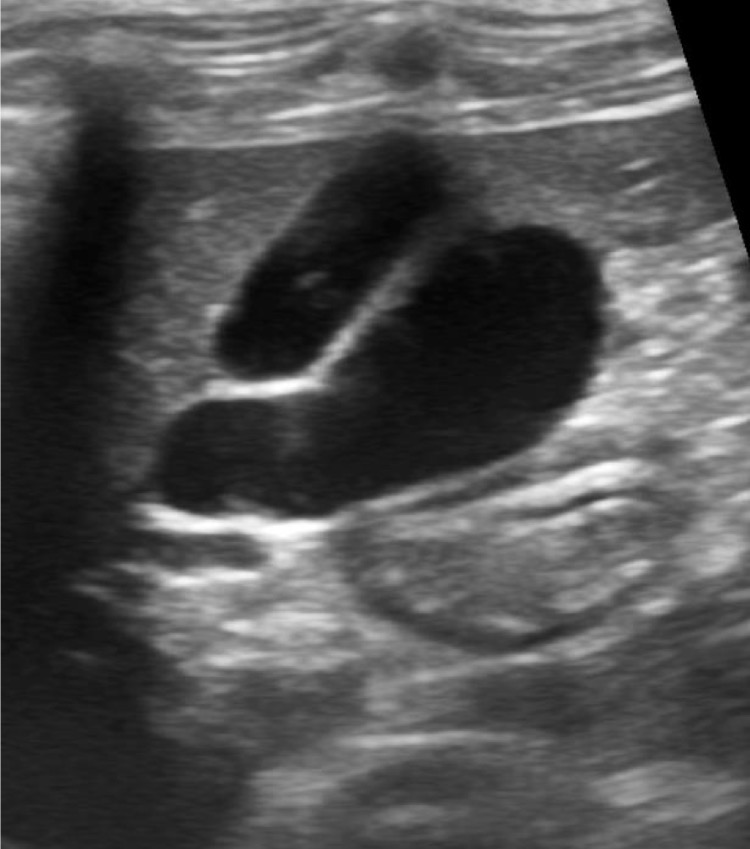

Bilobed gall bladder

What organ is this?